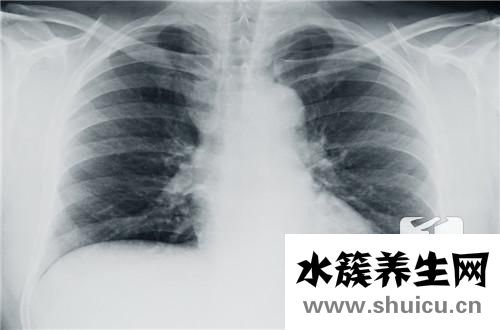

胸部是人體自然比照優良的位置。運用X線對心臟及肺的透過工作能力不一樣,在X線片或顯示屏上導致相對密度不一樣的影象,不需造影檢查就可以把肺內變病和心臟輪廊清晰地顯示信息出去。因此,胸部的X線檢查已變成運用最普遍的確診方式之一。

常見的胸部X線檢查方式有透視和拍片子二種。若有模糊不清原因的發熱、長期咳嗽、氣短、喘鳴、咯血、烏青、心悸及膈肌脊柱有畸型時,經醫生檢查覺得有必要,都能夠作胸部X線檢查。

胸部X線檢查針對小孩支氣管異物的確診有較高的精確性。針對肺部炎癥、肺不張、肺氣腫、氣胸、胸腔積液等也都能顯示信息,并掌握變病范疇和水平。一樣能顯示信息心臟和大血管的尺寸和形狀,橫膈變病如膈膨升、橫膈疝等。除此之外,胸部線片還可觀查到胸部骨骼的改變。但胸部x光片查驗有一定的局限,縱膈黑影內的人體器官和組織,如心臟、主動脈、靜脈、淋巴結、神經、食道、支氣管等,除開支氣管外其他均不可以辨別。